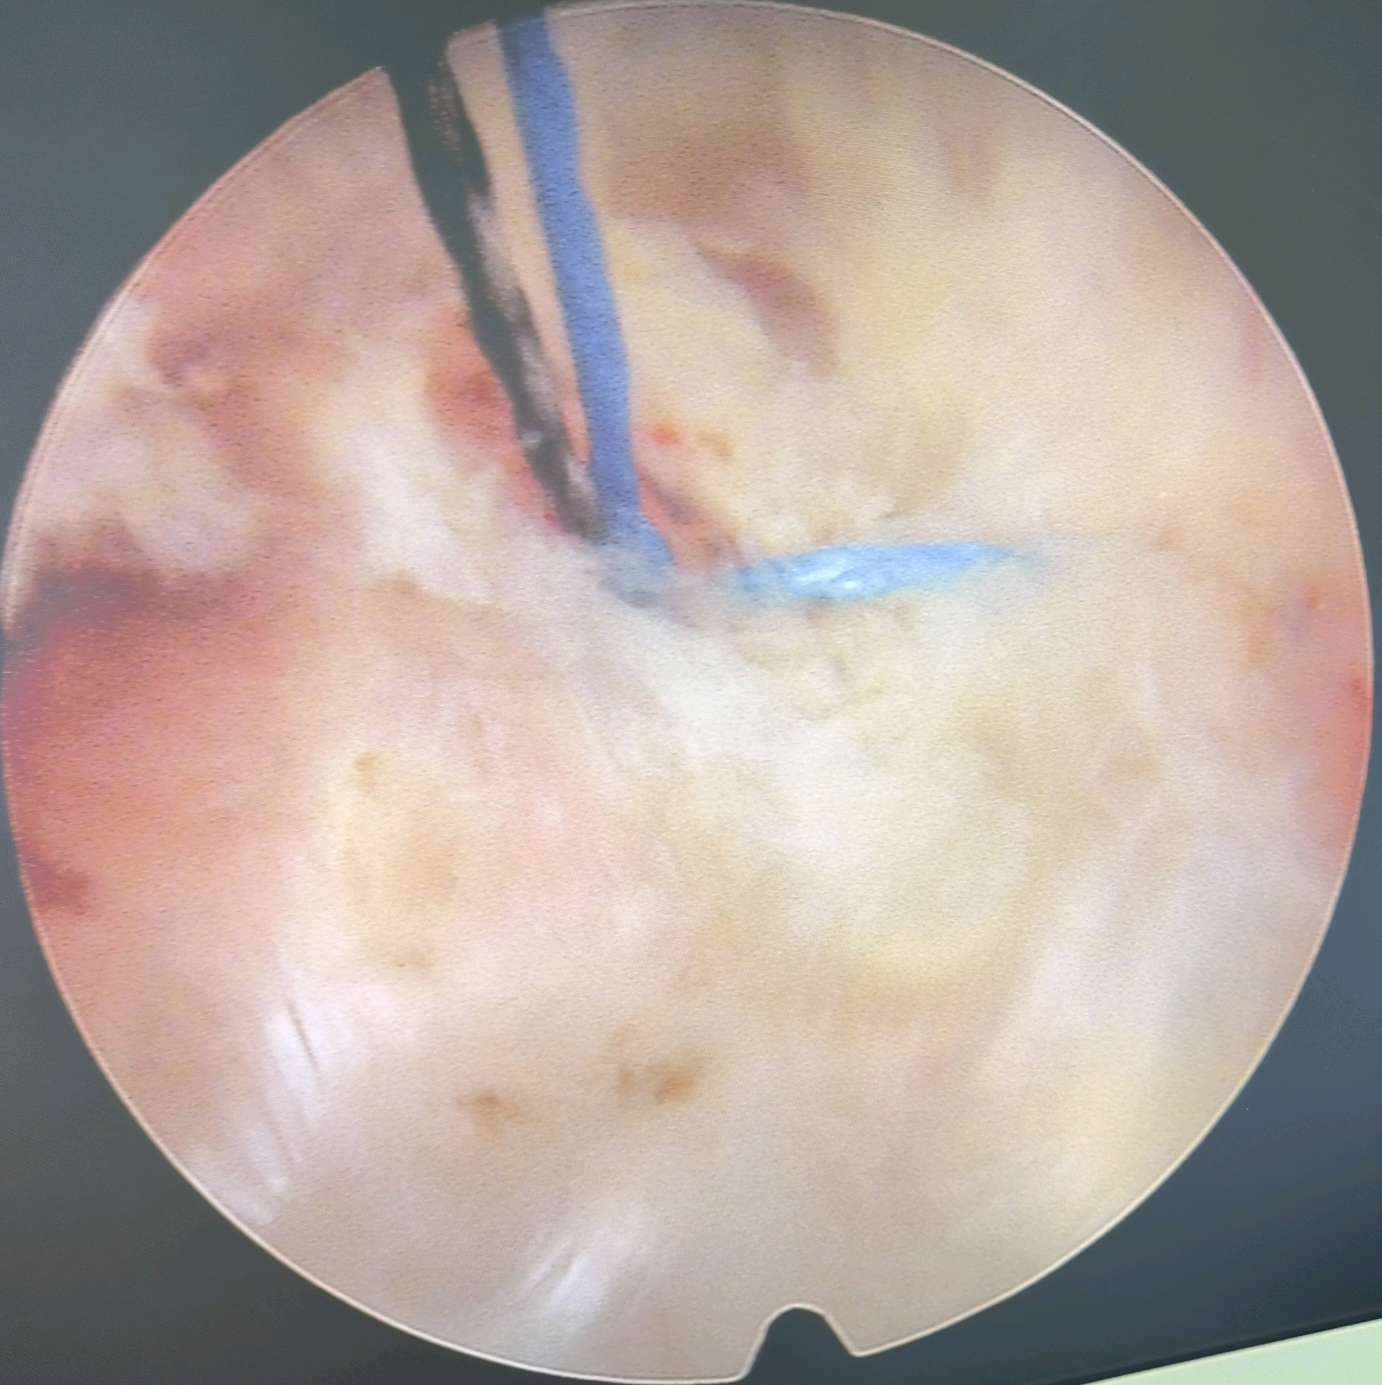

一个0.7cm大小的切口,下一个内镜进去,半个小时,全程无痛,就解决了神经受压,术中即感疼痛消失!

针对破裂的椎间盘,我们可以做一个纤维环缝合,就是把椎间盘的破裂口缝合起来,既保证了椎间盘的正常功能,又可以减少椎间盘突出的复发!

看着椎管内自由的神经根,心情是愉悦的,患者的心情更加愉悦,因为没有了那种钻心的疼痛!